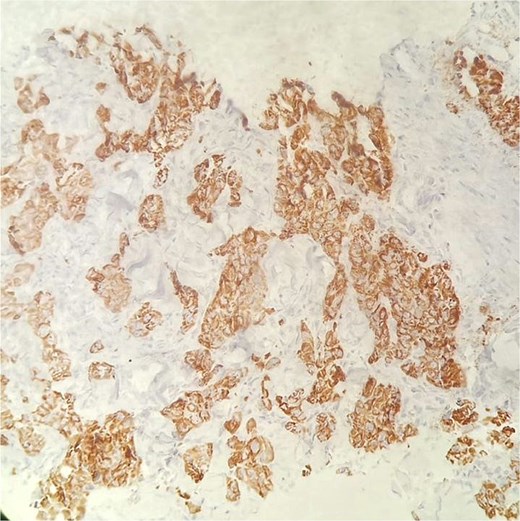

Immunohistochemical staining of the primary lung tumor.

(A) Tumour cells show strong cytoplasmic positivity for cytokeratin 7 (CK7).

(B) Diffuse positivity for cytokeratin 19 (CK19) is observed in the tumor cells. (C, D) tumor cells exhibit strong cytoplasmic staining for hepatocyte paraffin 1 (HepPar-1).

Distinguishing HAL from metastatic HCC remains a significant diagnostic challenge. In this case, immunohistochemistry played a crucial role; the tumor cells were positive for CK7, Hep-Par1, and CK19, and negative for TTF-1, Napsin-A, p40, AFP, and Glypican-3. This immunoprofile supports a primary pulmonary origin and helps exclude metastatic HCC.